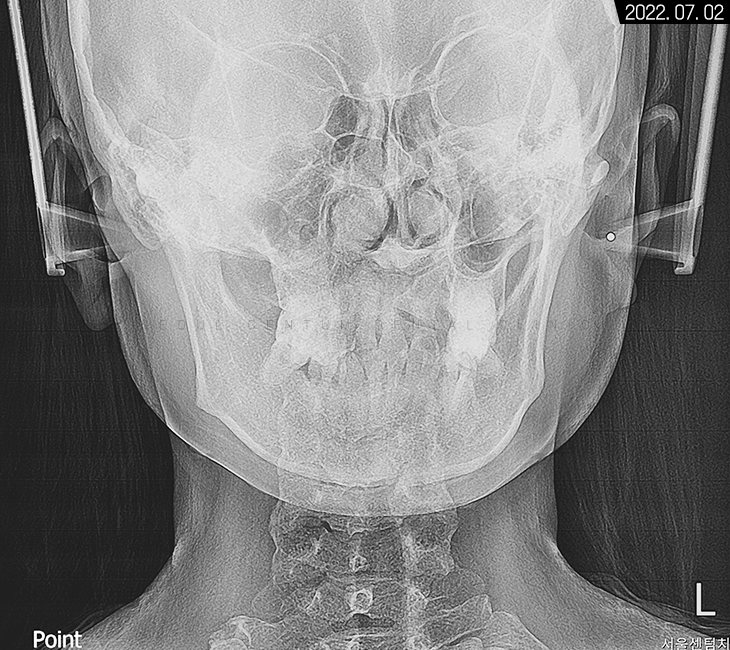

전면으로는 골격 비대칭 양상도 보여

다방면을 고려한 맞춤 치료를 진행하기로 했습니다.